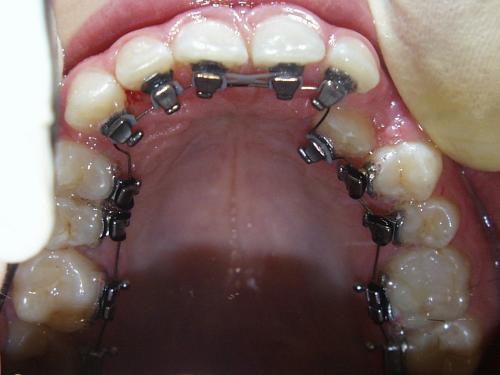

Fallbeispiel 6 zeigt die Einordnung eines gaumenwärts verlagerten linken oberen Eckzahns mittels Lingualapparatur nach chirurgischer Freilegung.

Bild 1: Beginn - Bild 2: nach 6 Monaten - Bild 3: nach 1 Jahr und 9 Monaten